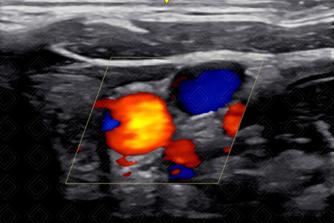

10. A critério, avaliar fluxo ao Doppler colorido (Figura 4). [cms-watermark]

Texto alternativo para a imagem Figura 4. Carótida e veia jugular ao Doppler colorido. Créditos: Dr. Igor Biscotto - Rio de Janeiro/RJ.